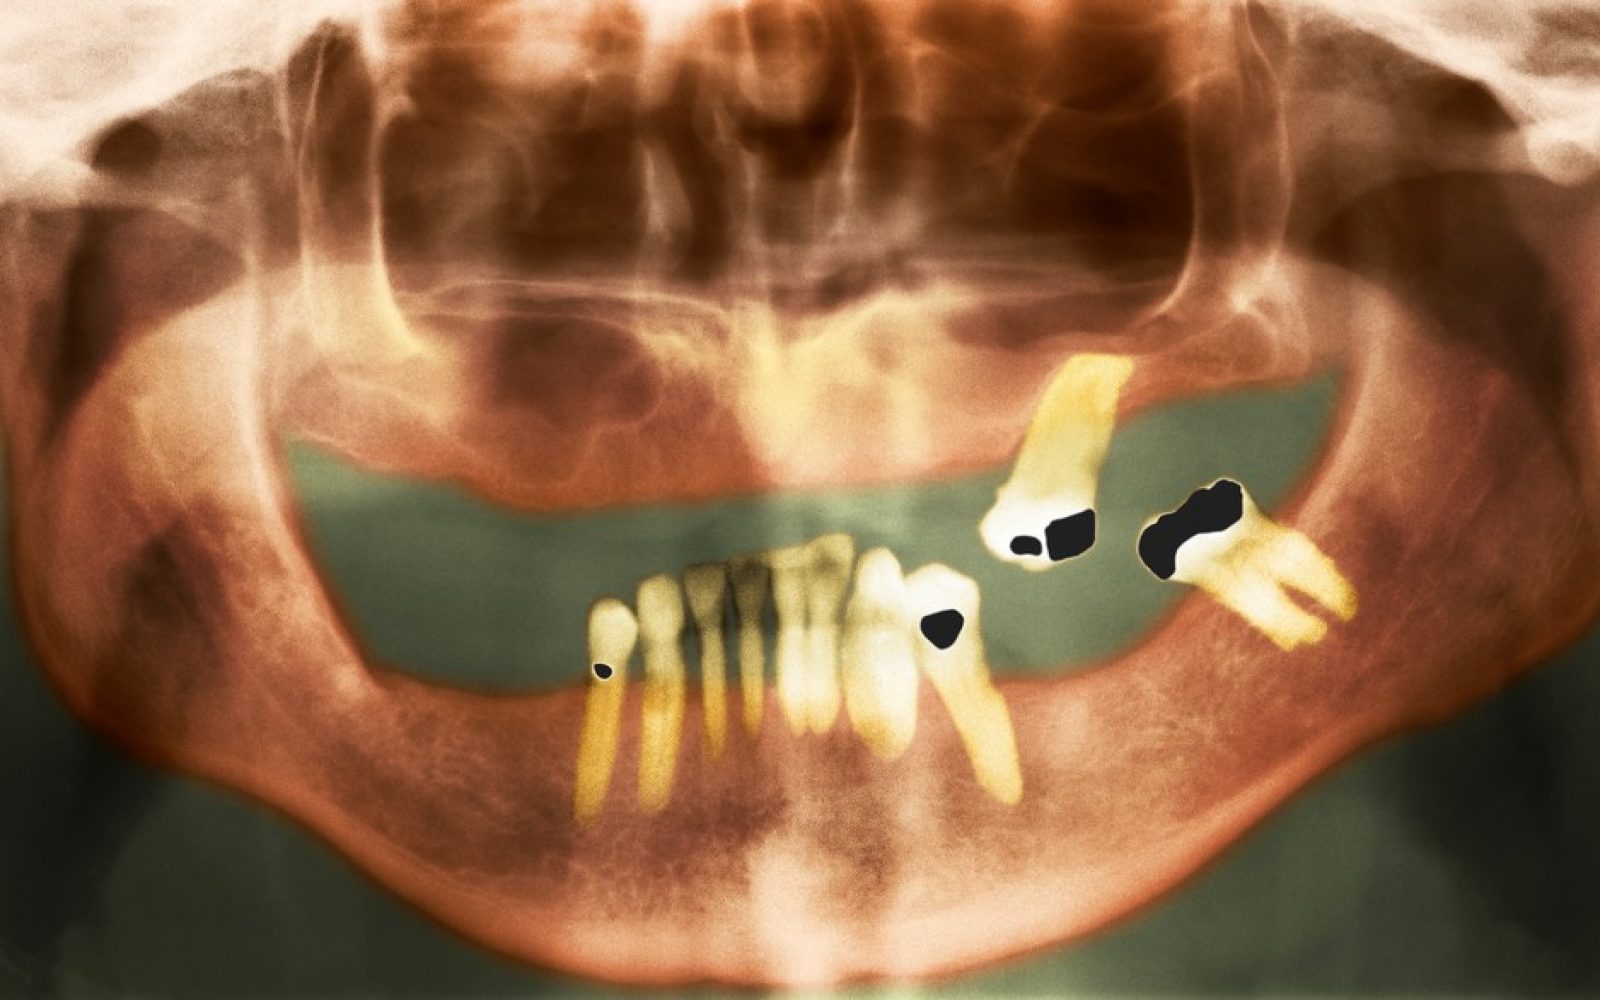

Zobna gniloba oziroma karies je najbolj razširjena bolezen ustne votline na svetu, pri čemer se ocenjuje, da nezdravljenje kariesa prizadene več kot 2 milijardi ljudi, kar povzroča resne zdravstvene težave.

Zobje so vsak dan izpostavljeni kislinam in sladkorjem, ki poškodujejo sklenino. Če so poškodbe prehude, se poškodovane grizne površine z jamicami in medzobni prostori zapolnijo s sintetično belo pasto.

“Pod tem polnilom lahko celice še vedno odmrejo. Zato je treba včasih zalivko izvrtati in ponovno očistiti. Poleg tega se vedno lahko pojavijo majhne razpoke, v katerih se lahko ugnezdijo bakterije in povzročijo nov razvoj kariesa.”